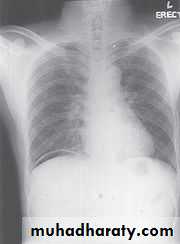

Pneumoperitoneum

Defined as free gas in the peritoneal cavityThe commonest cause is perforated peptic ulcer and two-thirds of such cases are recognizable radiologically

Pneumoperitoneum under the right hemidiaphragm is usually easy to recognize, but free gas under the left hemidiaphragm is difficult to recognize because of the overlapping gas shadows of the stomach and splenic flexure.

Gas under the diaphragm is much easier to diagnose on an erect chest film than on an upright abdominal film